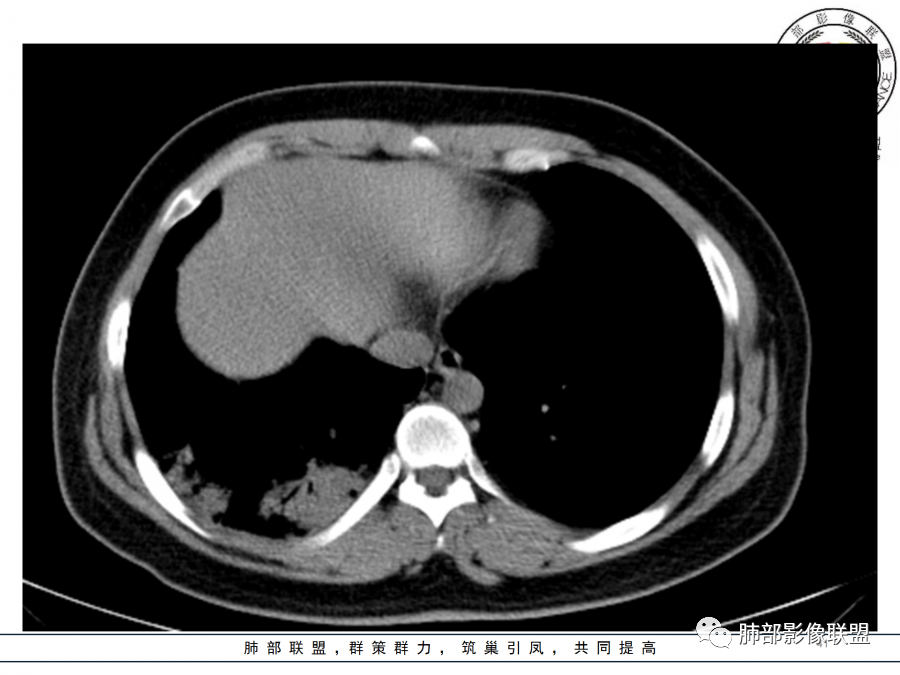

2.影像上怀疑其他病灶的理由有:

1)实变影为大小不等多中心性。

2)沿胸膜下分布趋势(不同于大叶性肺炎的肺叶“造型”)。

3)周围较大范围磨玻璃影及小叶间隔增厚。

4)病灶体积增大明显(叶间裂推移)。

3.腺病毒肺炎可以符合上述改变:实性密度,间质分布为主等。

4.隐球菌感染可以符合上述改变:胸膜下多中心实变密度为主,磨玻璃晕等。但隐球菌临床症状大多隐匿、迁延,影像变化缓慢。

5.本例患者血象高,影像渗出明显,尚不能排除混合感染可能。